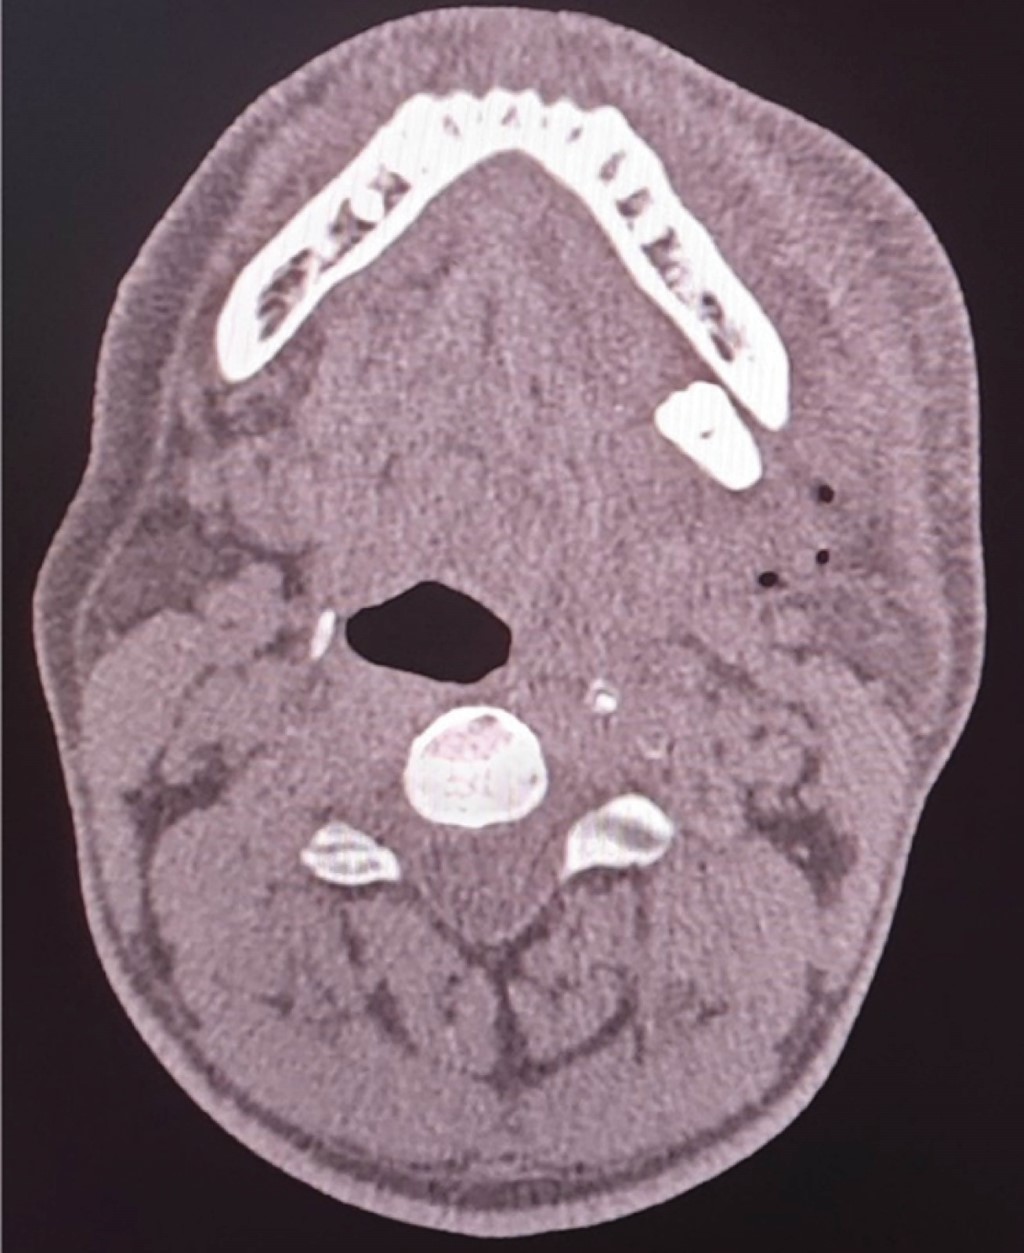

Tal como se refleja en el estudio realizado por Masui M y colaboradores denominado Displacement of lower third molar into floor of mouth: a single institutional experience,8 en el cual desarrollaron un análisis retrospectivo del manejo del tercer molar inferior desplazado hacia el piso de la boca, tomando en cuenta siete pacientes cuyo rango de edades iba de los 20-62 años, entre un periodo de tiempo que abarca del 2010-2020, el cual obtuvo como resultado: seis casos en donde el tercer molar fue desplazado hacia el espacio submandibular y un caso al espacio sublingual. Estas unidades dentarias o fragmentos dentarios, fueron retirados de piso de boca a través de un abordaje intraoral en seis casos, ya que únicamente un caso no se abordó; cuatro casos fueron abordados bajo anestesia general y dos casos bajo anestesia local, al igual que como expresan Tilaveridis I y asociados en el estudio denominado Displacement of maxillary third molar into the infratemporal fossa. A case report9 en donde se reportó el caso de un paciente masculino de 17 años de edad con desplazamiento de tercer molar superior izquierdo, luego de la evaluación de la tomografía computarizada se pudo evidenciar la presencia del tercer molar desplazado en la fosa infratemporal ipsilateral (Figura 1), su intervención fue bajo anestesia general, a través de un abordaje intraoral, en el cual la recuperación de la unidad fue de manera exitosa (Figura 2). De igual manera, Rivas y colegas en su estudio Tercer molar desplazado a fosa pterigomaxilar: reporte de caso5 presentan el caso de un paciente de sexo femenino de 16 años de edad, durante la cirugía de los terceros molares, la unidad 28 fue perdida de vista por parte del operador, indicaron radiografías panorámicas y tomografía de haz helicoidal, después de su evaluación se evidenció la ubicación de la unidad, el cual se encontró en la fosa pterigomaxilar (Figuras 3 y 4). Se realizó un abordaje intraoral bajo anestesia local, hasta alcanzar la unidad dentaria desplazada y recuperarla de manera exitosa.

Figura 1

Figura 2